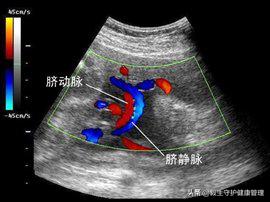

对此,小毅想告诉各位妈妈:初为人母,怀孕期间不时会遇到身体上某些指标的异常,切记不要惊慌。上面妈妈提问关于单脐动脉的问题,实际上指胎儿的脐带血管只有一条脐动脉和一条静脉的现象,名为单脐动脉现象。

孕妇怀孕后在胚胎时期,如果脐动脉发育不良会导致单脐动脉症状,胚胎时期,脐动脉由背主动脉发出的一对尿囊动脉演变而成。若一条脐动脉发育不良而萎缩,或在早期(3.0~4.0mm胚胎体蒂)暂时出现单脐动脉时期(即左、右脐动脉合并成一条血管)持续下去均可致单脐动脉。血栓时引起单脐动脉的一大原因,因为血栓的形成可能会导致某一条脐动脉萎缩。长久下去,就会形成单脐动脉。